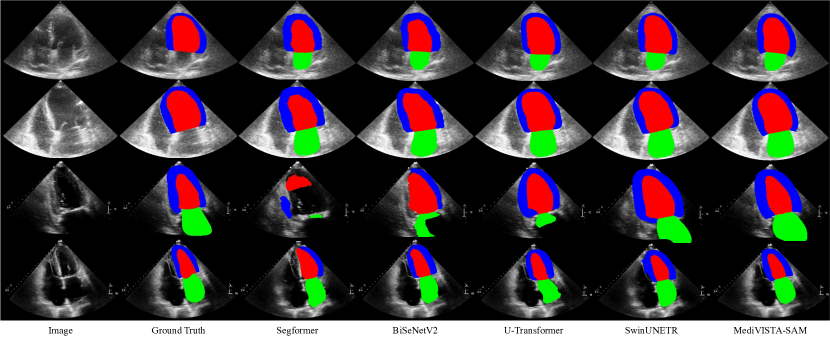

Refer to caption

Figure 3: The visual comparison of segmentation results on CAMUS dataet (rows 1-2) and our in-house dataset (rows 3-4). The blue, red and green regions denote the left ventricle endocardium, epicardium and left atrium, respectively. Please note that the CAMUS sequential dataset only includes labels for LVendo𝐿subscript𝑉𝑒𝑛𝑑𝑜LV_{endo} and LVepi𝐿subscript𝑉𝑒𝑝𝑖LV_{epi}.

We have conducted an extensive evaluation of our methods in two datasets: camus dataset and in-house multi-center dataset. We compare state-of-the-art(SOTA) methods including six CNN-based methods: LUNet [14], Deeplabv2 [3], [39], Enet,[21] , ICNet [37], and BiSeNetV2 [35] and three transformer based methods: SegFormer [34], U-transformer [22], and SwinUNETR [9]. Table 1 presents the results for both the CAMUS and in-house datasets. While the CAMUS dataset comprises two labels, LV endo and LV epi, the in-house dataset extends to three, incorporating LA.

For CAMUS dataset, all the methods demonstrated comparable segmentation performance for LV endo and LV epi. As detailed in Table 1, our model outperformed the next best method by enhancing the Dice score by 1.9% and 0.2%, and improving the temporal smoothness by 0.03. It’s crucial to recognize the inherent challenges of the CAMUS dataset, which have a high inter and intra-observer variability, reaching up to 6% in the ground truth data [15]. This variability can be further observed in Figure 3 and Table 1. Furthermore, we have included our analysis both SAM-based and non-SAM-based methods. However, for SAM without prompt, and one point prompt, we find they fail to generate plausible results, e.g., w/o prompts generate segmentation of scan of region area totally different from what we want as in Figure 4. Furthermore, when it comes to segmenting for the LVepi𝐿subscript𝑉𝑒𝑝𝑖LV_{epi}, which surrounds the LVendo𝐿subscript𝑉𝑒𝑛𝑑𝑜LV_{endo}, none of the prompt methods achieve successful segmentation. Therefore, we only include the results using two points prompts and box prompts as in Table 1. We presented all results without any post-processing, enabling a direct comparison of segmentation performance.